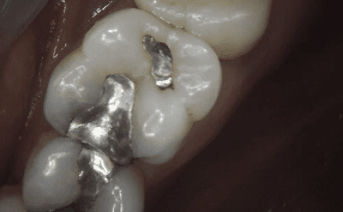

Our composite dental fillings in Atlanta, Georgia, not only fill in cavities, but can treat various cosmetic treatments by filling in teeth that have been damaged or demineralized. Schedule your treatment at Smiles of Atlanta with our dentist, to see if you need a composite dental filling from Dr. Ed Trizzino. Call 770-777-0808 today.